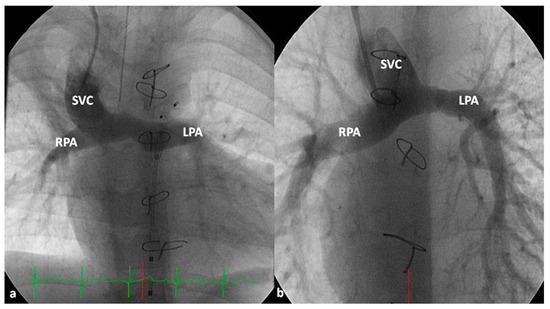

At about the age of six months, a bidirectional Glenn procedure [80] is performed. In this procedure, the superior vena cava (SVC) is disconnected from the right atrium and anastomosed to the PA so that the blood from SVC is directed into both branch PAs, thus the name bidirectional Glenn (Figure 8).

In patients with an additional persistent left SVC, a bilateral, bidirectional Glenn procedure (Figure 9) is performed especially if the bridging left innominate vein is small or absent.